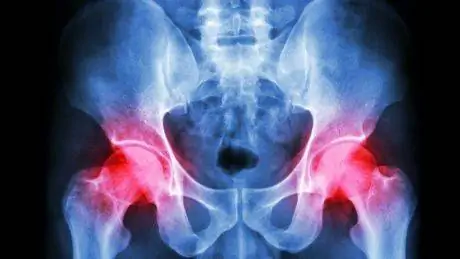

Бедро представляет собой шаровидный сустав. Гнездо находится в большой тазовой кости, а подушечка - в верхней части бедренной кости. Слой ткани, называемый верхней губой, надежно удерживает шарик в лунке. Бедро поддерживают несколько мышц и сухожилий, и они, как и сам сустав, могут бытьповреждены во время тренировки.